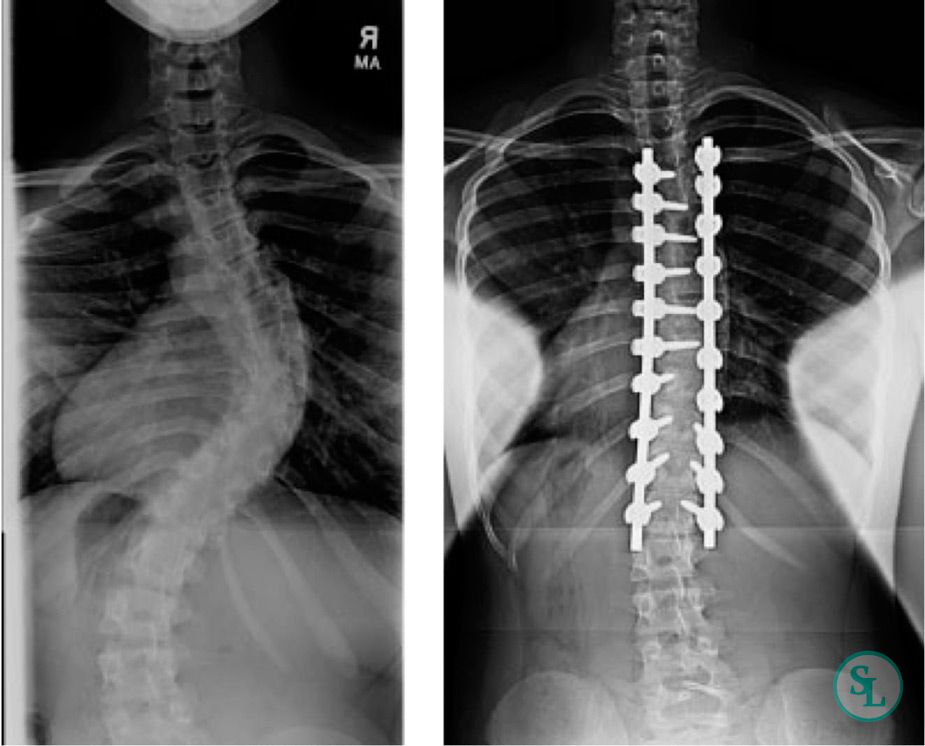

Оқушылар рентгенография нәтижесіне қарай дұрыс және ауру түсірімді ажыратады. Дене сымбатының бұзылу себептерін айтады.

Мәтін: Айгүлдің ұзақ уақыт бойы компьютер алдында отыруынан омыртқа жотасының ауырсынуын сезінетінін айтып, ата-анасына шағымданды. Келесі күні ата-анасы Айгулді дәрігер қарауына апарды. Дәрігер омыртқа жотасының рентгенографиясын жасауды ұсынады.Нәтижесінде денсаулыққа әсер ететін маңызды мәселе бар екені анықталды. Дәрігер, Айгулге арнайы жаттығулар жасап, омыртқа жотасын қалпына қалпына келтіруіне бірнеше дұрыс кеңестер берді. Сұрақ: 1 Білу: Тірек қимыл жүйесі қандай негізгі мүшелерден тұрады?

3. Қазақстан мен Шведция мемлекеттерін салыстырмалы түрде талдау жасай алды Жалпы балл-1 Дескриптор: рентгенография нәтижесіне қарай дұрыс және ауру түсірімді ажыратады Жалпы балл-1 Дескриптор: 1. Тірек қимыл жүйесінің, мүшелерден атайды Жалпы балл-1 2. Дене қалпының дұрыс болмауы тірек-қимыл жүйесіне әсер етуін сипаттайды Жалпы балл-1 3.Омыртқаны нығайтуға арналған бір неше жаттығуларды ұсынады Жалпы балл-1 4.Компьютер алдында дұрыс отырмаудың және ауыр жүк көтерудің омыртқаға әсерін талдайды. Жалпы балл-1